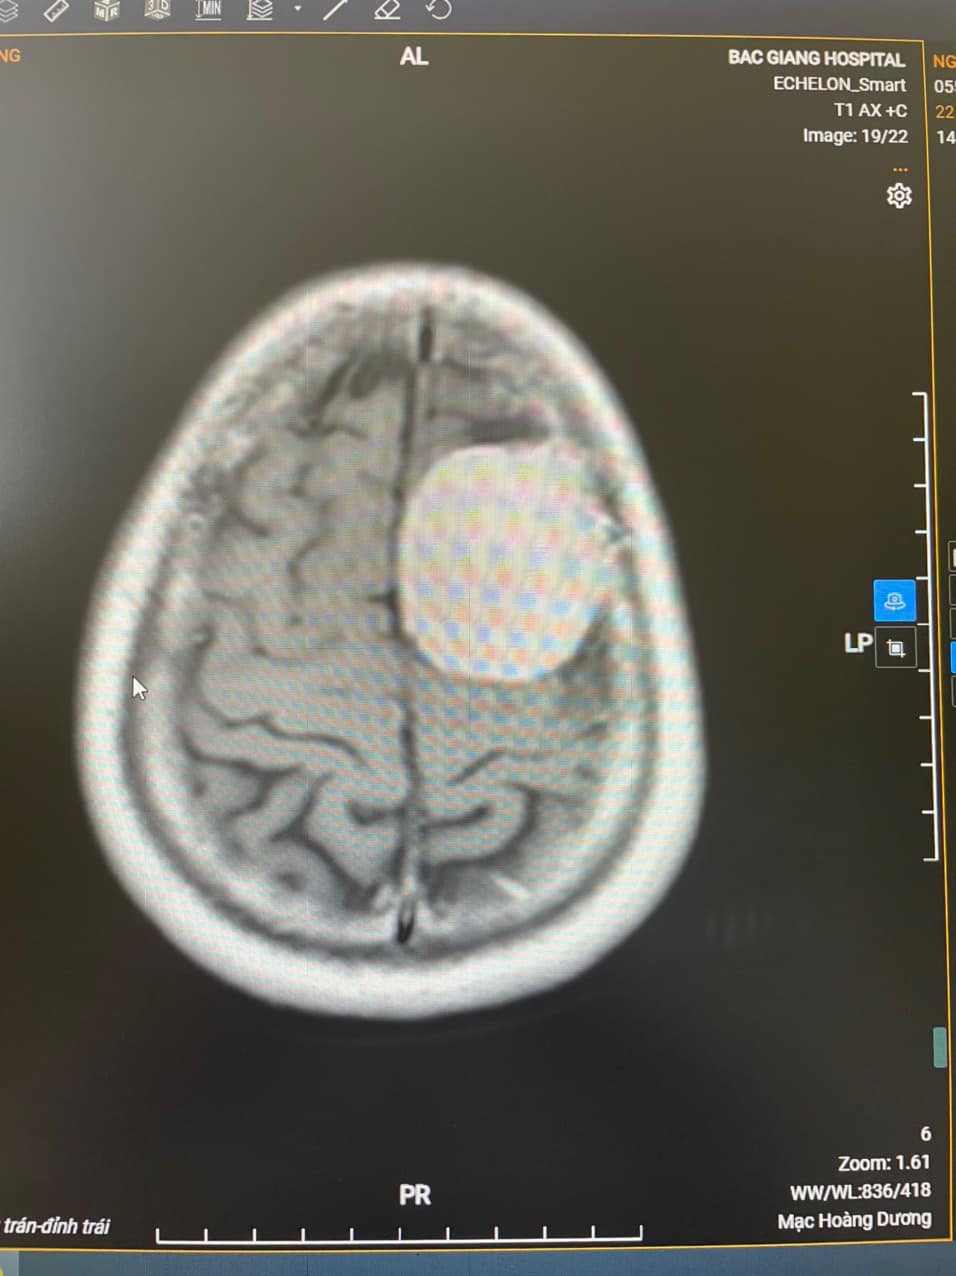

Sau khi vào khoa Ngoại thần kinh của Bệnh viện Đa khoa tỉnh, bác sĩ đã tiến hành khám và chỉ định chụp cộng hưởng từ có tiêm thuốc cản quang để tìm nguyên nhân thì thấy một khối u có kích thước 36x48x54mm vùng trán đỉnh trái của người bệnh. Bệnh nhân được chẩn đoán là u não vùng trán đỉnh trái. Các bác sĩ của Bệnh viện Đa khoa tỉnh đã tiến hành hội chẩn với chuyên gia đầu ngành thần kinh sọ não của Bệnh viện Hữu Nghị Việt Đức và sau đó đi tới quyết định phẫu thuật lấy khối u trên. Trước đây, tại Bệnh viện Đa khoa tỉnh đã thực hiện nhiều ca mổ u não, u màng não nhưng chưa từng thực hiện ca phẫu thuật lấy u não nào có kích thước lớn lại gần trung khu vận động như vậy nên người nhà người bệnh còn thấy phân vân. Tuy nhiên, sau khi được nghe các bác sĩ giải thích, tư vấn, người nhà bệnh nhân đã hoàn toàn tin tưởng và đồng ý thực hiện phẫu thuật. Ca phẫu thuật kéo dài hơn 4h đồng hồ, kíp mổ gồm BS.CKII Mạc Hoàng Dương, Trưởng khoa Ngoại thần kinh; BS Nguyễn Minh Hải, khoa Phẫu thuật Gây mê hồi sức cùng các cộng sự; dưới sự giúp đỡ của chuyên gia TS.BS Bùi Huy Mạnh, Khoa Phẫu Thuật Thần kinh I, Bệnh việt Hữu Nghị Việt Đức. Với ê-kíp phẫu thuật có kinh nghiệm chuyên môn sâu cùng các trang thiết bị hiện đại, khối u lớn trong não đã được lấy ra trọn vẹn.

BS.CKII Mạc Hoàng Dương, Trưởng khoa Ngoại thần kinh, trực tiếp thực hiện phẫu thuật cho bệnh nhân X cho biết: “Khối u trong não của người bệnh rất lớn, phát triển vào sâu trong tổ chức não, lại nằm ở vùng sát với rất nhiều hệ thống mạch máu, thế nên nguy cơ làm đứt và chảy máu trong khi phẫu thuật là rất cao đòi hỏi sự tập trung cao độ, phối hợp nhịp nhàng, chặt chẽ giữa bác sĩ phẫu thuật và bác sĩ gây mê”.